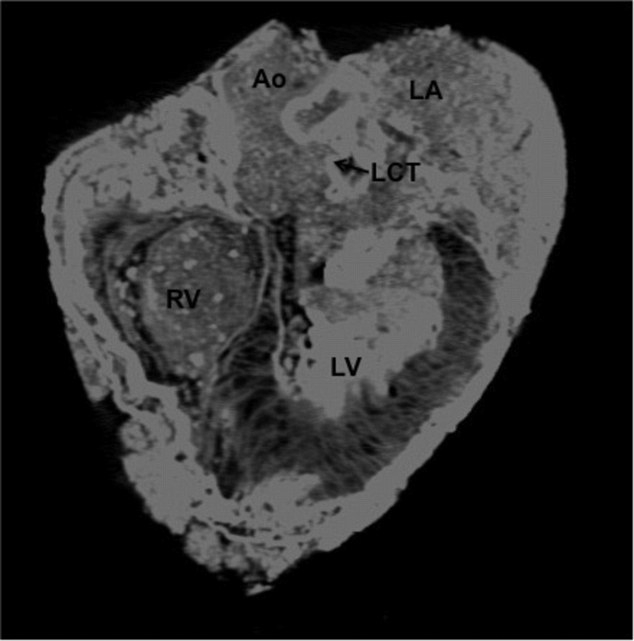

Bilim insanları, mumyalanmış bedenleri MR cihazlarında inceledi.